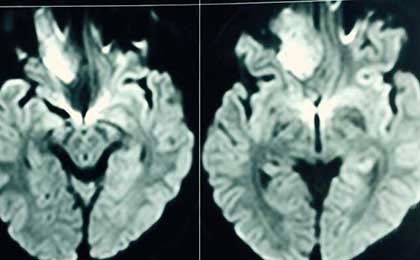

frontal epidermoid post

• frontal epidermoid post